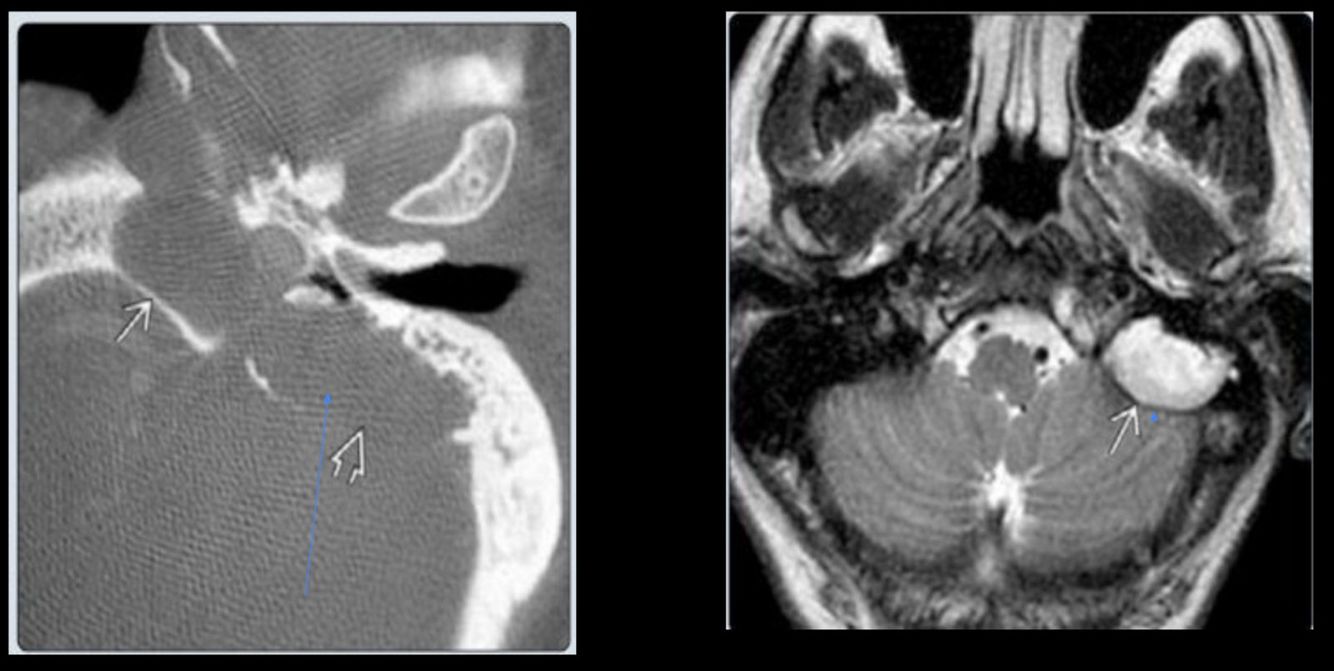

Colesteatoma

¿Cuál es una pista característica del colesteatoma?

Destruye hueso

En la RM del colesteatoma, ¿cómo se observa en T2?

Hiperintensa